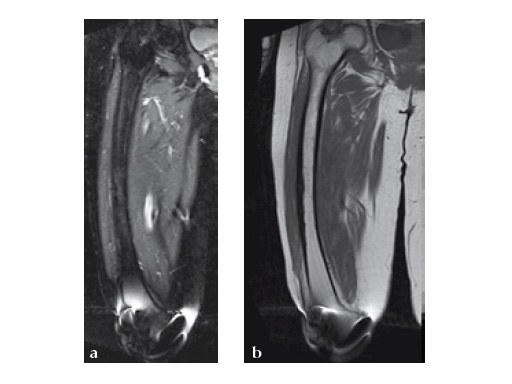

No edema indicated a stress fracture (see Fig 4a-b).